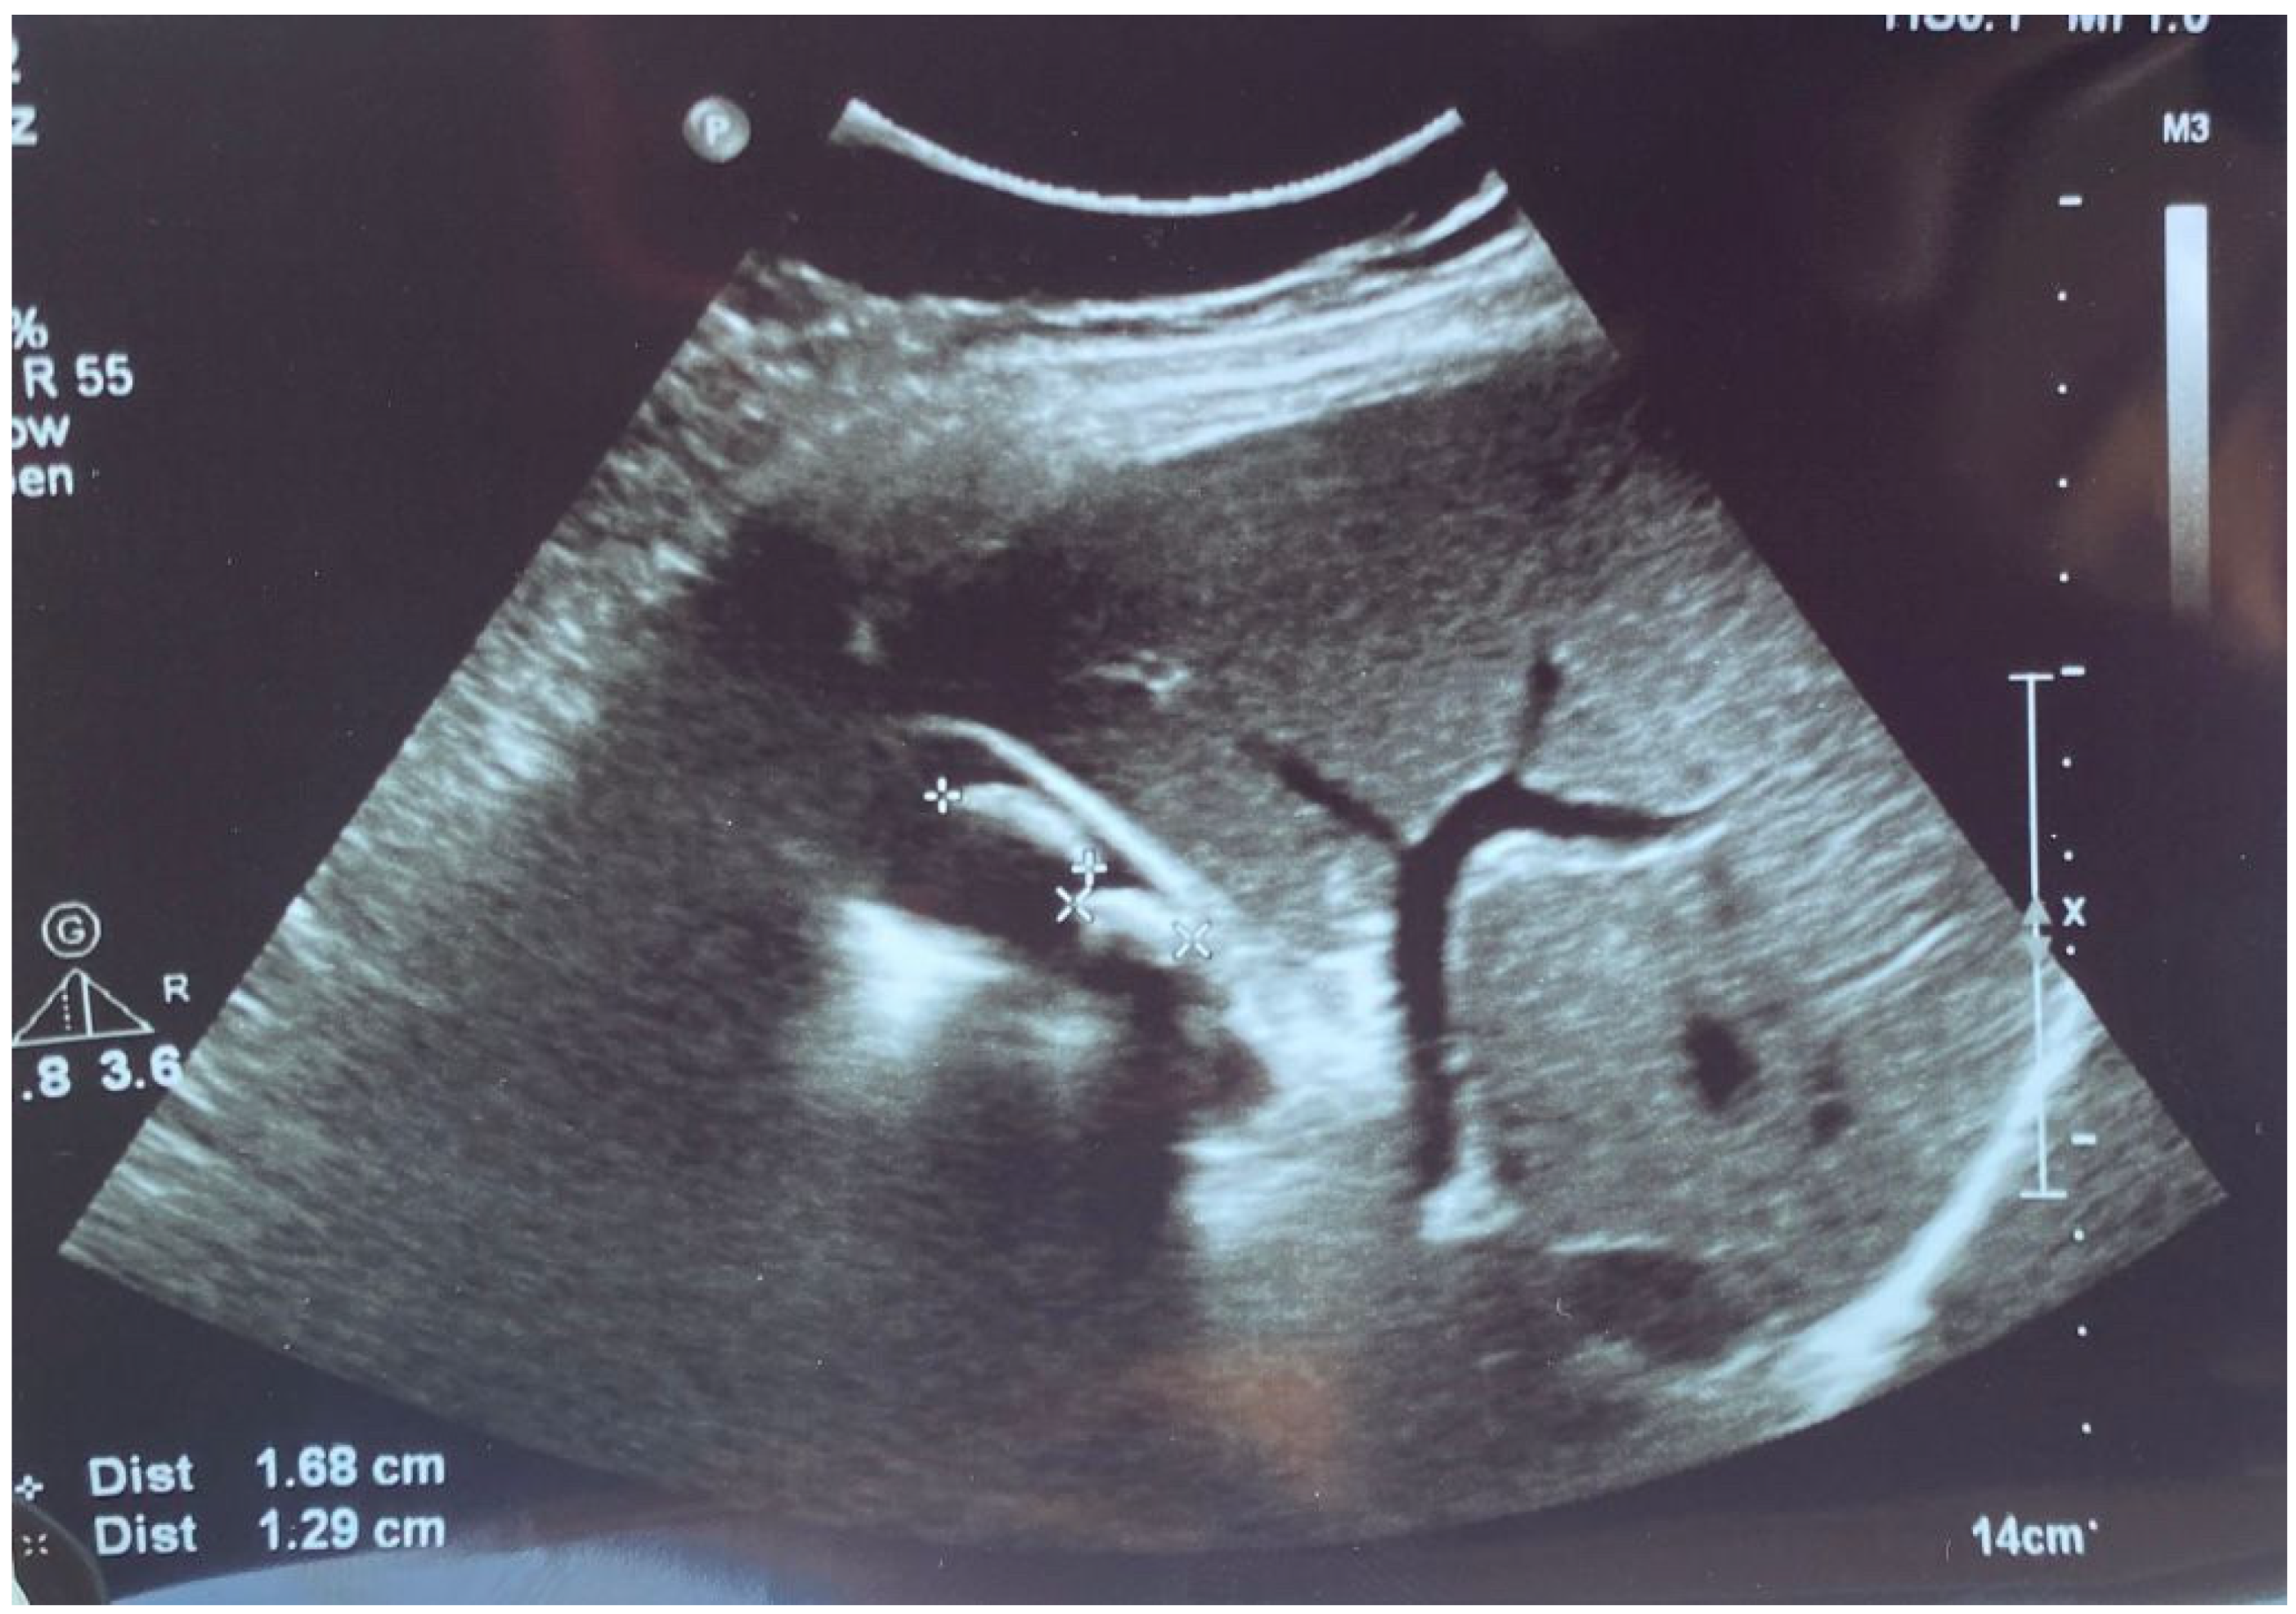

The patient performed an abdominal ultrasound, which revealed multiple gallstones, but the central bile duct was in a normal range value (Figure 1), so acute cholangitis was initially suspected.

Figure 1.

Abdominal ultrasound images of the gallbladder showed lithiasis (two calculi of 1.68 cm and 1.29 cm) associated with acoustic shadows in the transverse plane.